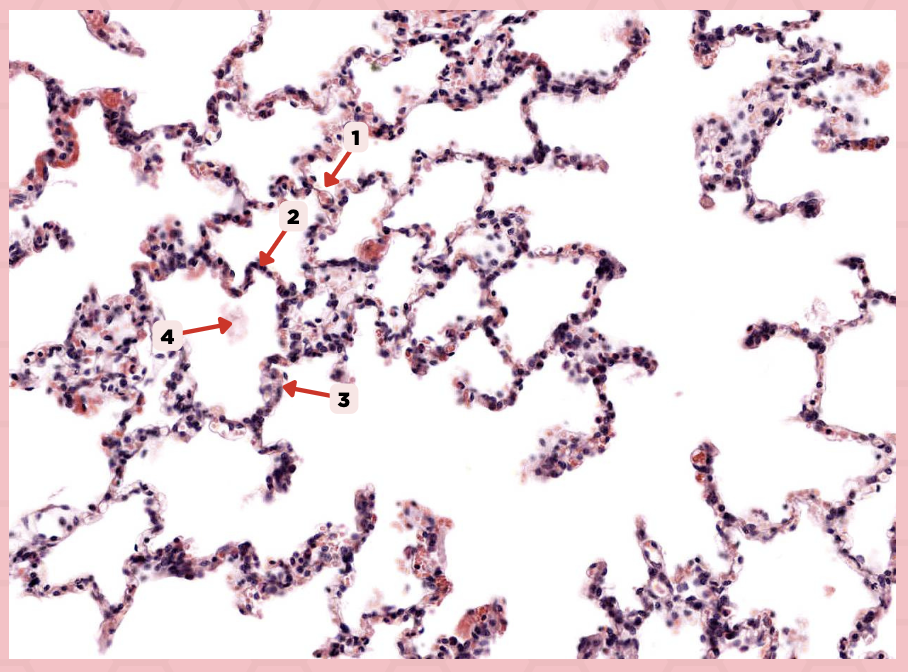

Interalveolar septum

Identify the structure labeled as 1.

Type I alveolar cell

Identify the structure labeled as 2.

Type II alveolar cell

Identify the structure labeled as 3.

Pulmonary Alveolar Macrophages (Dust Cells)

Identify the structure labeled as 4.

Pulmonary Alveolar Macrophages (Dust Cells)

What are the most numerous cells inside the alveoli?

Pneumocyte Type I

Which of the following labeled structures covers 95% of the alveolar surface?

Type I alveolar cell

Identify the structure labeled as 1.

Type II alveolar cell

Identify the structure labeled as 2.

Pulmonary Alveolar Macrophages (Dust Cells)

Identify the structure labeled as 3.

Endothelial Cells

Identify the structure labeled as 4.